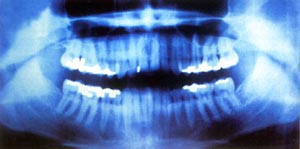

受這次偶然發現的激勵,倫琴放下其他研究項目,集中精力調查X射線的特性。經研究他發現:X射線能使許多物質發光;X射線可以穿透不透光物質,他特別注意到,X射線能夠透過他的肉體,只是為骨骼所阻,把手放在陰極射線管和螢光屏之間,能夠在螢光屏上看到手骨的影子;X射線是直線,它與充電粒子束不同,不因磁場而折射……最後,倫琴以高超的實驗技巧取得了9項關於X光重要性質的成果。由此可見,倫琴不是僅僅向螢光紙板方向看一眼就成為發現X光的巨人的,而是依靠敏銳的觀察力、科學的預見力、準確的判斷力、高超的實驗力才成為傑出的科學家。1901年第一屆諾貝爾物理學獎評選時,29封推薦信中就有17封集中推薦他。倫琴最終獲得了第一次諾貝爾物理學獎金。 1923年,倫琴在德國慕尼黑病逝,終年78歲。關鍵詞:X射線,倫琴射線